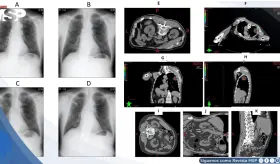

Experto destacó los progresos en el tratamiento del cáncer renal mediante cirugía robótica e inmunoterapia, mientras alertó sobre videos fraudulentos que utilizan su imagen para vender medicamentos falsos.